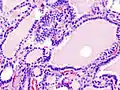

The same three treatments used with humans are also options in treating feline hyperthyroidism (surgery, radioiodine treatment, and anti-thyroid drugs). There is also a special low iodine diet available that will control the symptoms providing no other food is fed; Hill's y/d formula, when given exclusively, decreases T4 production by limiting the amount of iodine needed for thyroid hormone production. It is the only available commercial diet that focuses on managing feline hyperthyroidism. Medical and dietary management using methimazole and Hill's y/d cat food will give hyperthyroid cats an average of 2 years before dying due to secondary conditions such as heart and kidney failure.[62] Drugs used to help manage the symptoms of hyperthyroidism are methimazole and carbimazole. Drug therapy is the least expensive option, even though the drug must be administered daily for the remainder of the cat's life. Carbimazole is only available as a once daily tablet. Methimazole is available as an oral solution, a tablet, and compounded as a topical gel that is applied using a finger cot to the hairless skin inside a cat's ear. Many cat owners find this gel a good option for cats that don't like being given pills.